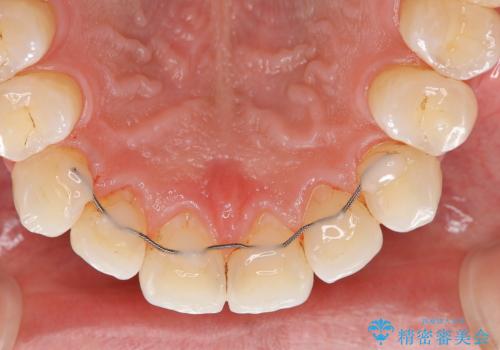

また、以前他院にて矯正治療を行い、前歯の裏側には保定装置がついていることで磨きにくいため機械的に細かい部分のクリーニングも希望とのことでした。

エアフローワンは、特殊なパウダーを混ぜた水を水面にジェット噴射することでバイオフィルム(プラーク)・ステイン(着色)・早期歯石を天然歯やインプラント周囲から除去することが可能な歯面清掃器具です。

従来の荒い研磨剤などを用いた歯面への負担が大きいクリーニングとは異なり、歯質の負担を最小限にした歯面清掃と歯周ポケット内のメンテナンスを行えます。